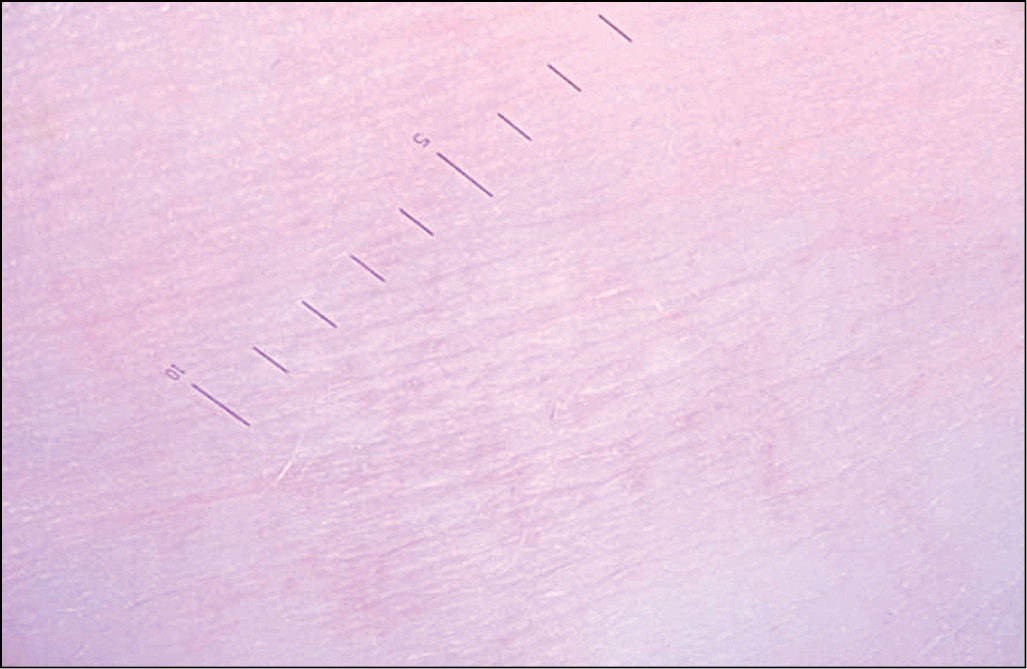

Рис. 12. Размытые границы пятна

Размытые границы пятна (рис. 12) – плавный переход от здоровой кожи к депигментированной в виде разрежения насыщенности пигмента. Появление размытых границ пятна у пациентов с нестабильной стадией и репигментацией (у 32; 94,1%, и 14; 77,8%, соответственно) встречалось значимо чаще, чем у пациентов со стабильной стадией витилиго (у 3; 27,3%); рис. 13. Согласно χ2-критерию Пирсона и расчёту значимости методом Монте-Карло, на стадиях обнаружены значимые различия частоты появления размытых границ пятна (р = 0,001). Паттерн указывает на прогрессирование процесса на границе здоровой кожи и витилиго, что выражается плавным уменьшением пигмента. Клинически наблюдается трихром.